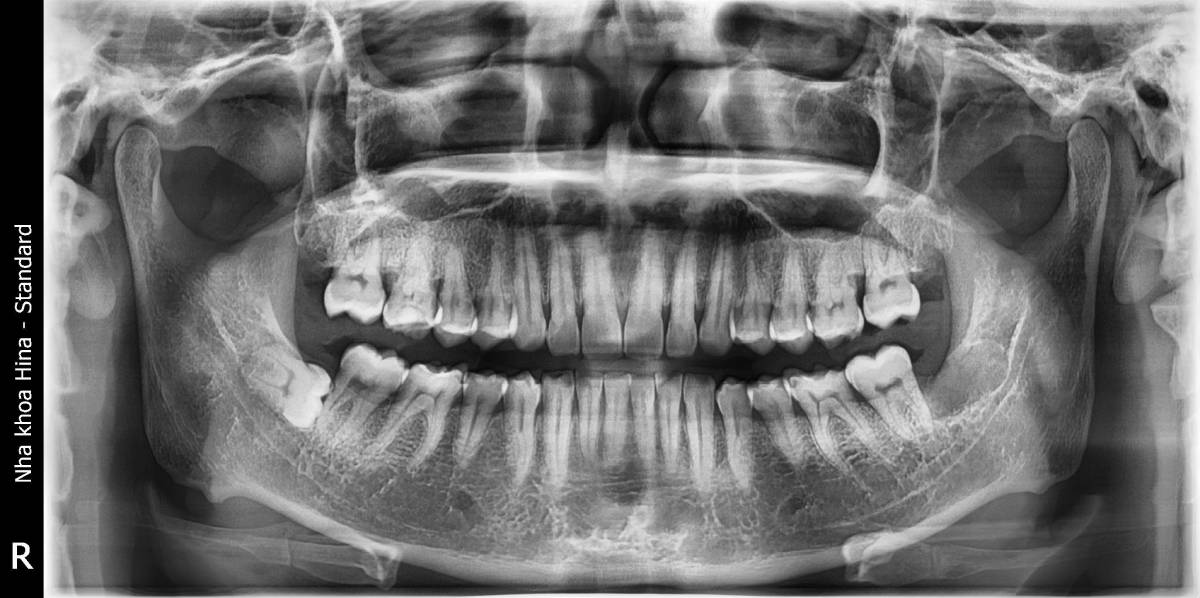

Nếu răng khôn mọc nghiêng nhưng không gây đau, không ảnh hưởng đến răng khác và dễ vệ sinh thì bác sĩ có thể chỉ định theo dõi định kỳ. Tuy nhiên, bạn vẫn nên chụp X-quang 6 tháng/lần để kiểm soát tình trạng.

Thăm khám và chụp X-quang để xác định vị trí, thế mọc răng.